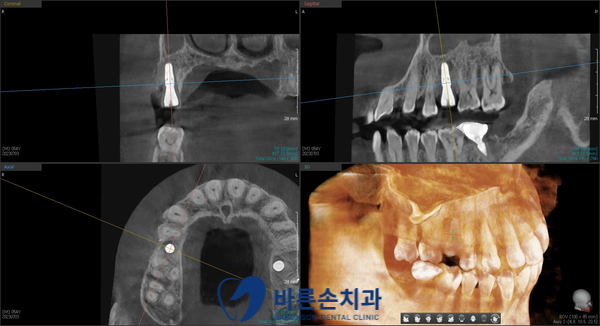

임플란트 수술 직후 찍은 3D-CT 사진입니다

CT 상에서도 기존 치아가 있던 위치에

임플란트가 안정적으로 수술된 것을 확인하고

당일 진료가 마무리되었습니다^^